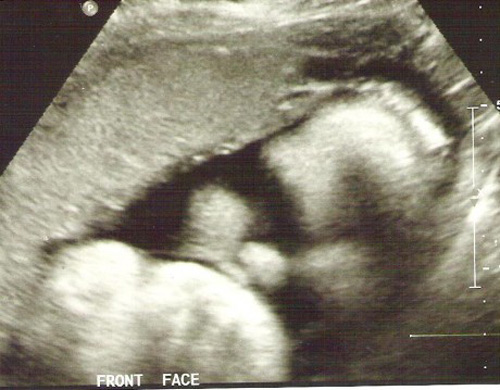

Old  Default Bà mẹ người Mỹ vui mừng khi mang thai,tuần 22 siêu âm nhận kết quả như "sét đánh".

Một bà mẹ người Mỹ vô cùng vui mừng khi biết mình mang thai.Tuy nhiên đến tuần thứ 22 tiến hành siêu âm thai nhi,quá bất ngờ khi nhận được kết quả.Bà mẹ chia sẻ câu chuyện của mình khiến nhiều người cảm động.

Chúng tôi lại chờ đợi đến tuần 22 mới quyết định siêu âm để xem hình thái của con. Vậy nhưng sau 22 tuần chờ đợi, chúng tôi lại nhận về một tin như “sét đánh”.

Nữ y tá siêu âm cho tôi nói chúng tôi có một bé gái nhưng cô không thể nhìn thấy bàn chân bên trái của con bé đâu. Y tá nói cô phải đưa kết quả cho bác sĩ kiểm tra lại.

Tại lần siêu âm thứ 2 ở tuần 26 thai kỳ, bác sĩ đã khẳng định lại một thực tế là con gái tôi không có bàn chân trái nhưng vẫn có khớp gối. Ngoài ra, bàn tay con bé dường như nắm chặt và không thể mở ra. Ông giải thích thêm rằng có thế bé đã gặp dị tật do di truyền. Sức khỏe tại thời điểm đó của con rất tốt, chỉ là không có bàn chân bên trái và bàn tay không mở được.